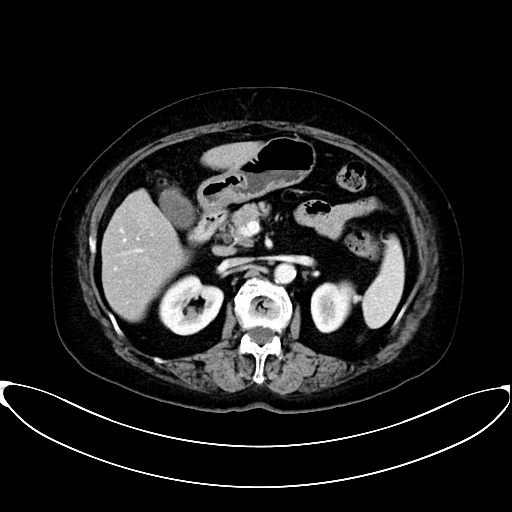

70多岁的王女士就是其中一位。2021年,王女士诊断为胆囊癌侵犯肝脏、腹壁,初始评估无手术机会,在潞河医院肿瘤中心经过精准抗肿瘤内科治疗(抗HER-2靶向药物联合PD-1单抗)后获得了手术切除机会,术后病理提示未见残存肿瘤细胞,目前处于无瘤生存状态。

治疗后